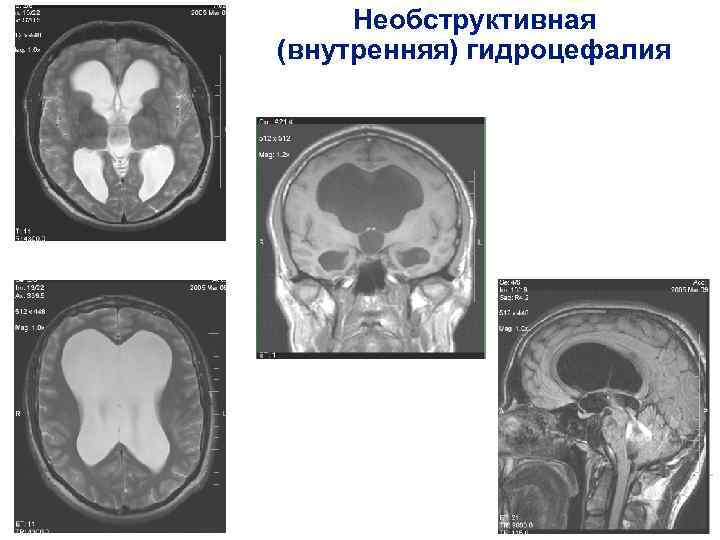

Признаки умеренно выраженной наружная

Признаки умеренно выраженной наружная 113 фото